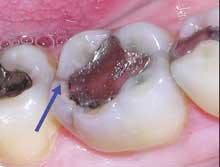

Consider the mush and recurring decay you often find under unbonded amalgams, plus the fractures under weakened cusps or brazenly dead center in sub-amalgam tooth structures. (This is common in baby boomers when canine guidance has been lost.) When I remove an old, defective, amalgam restoration, I recall turning over a rock embedded in the earth and half looking away for fear of finding something scary. Use that simile when recommending replacement of old alloys. It will help you explain the situation (Figures 3 and 4).